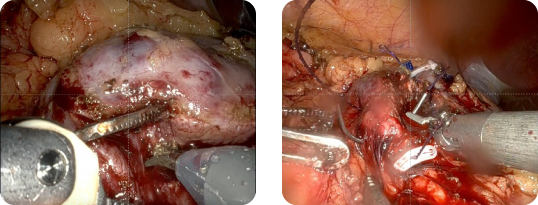

欧米を中心に導入され、近年ではアジア地域においても確実に普及されている手術用ロボット。日本においては、平成21年11月に薬事承認され、平成24年4月より、前立腺癌の手術につき保険承認されました。その手術ロボット「ダヴィンチ」が2012年4月、当院に導入されました。

初期の前立腺癌の治療法として開腹・腹腔鏡手術や放射線療法・内分泌療法などがあり、年齢・癌細胞の種類や他に患っている病気の有無により治療法が決定されています。

手術は最も根治性の高い治療ですが、一方で「尿失禁」や「性機能低下」の恐れが指摘されておりました。この手術ロボットは上記の問題を改善できるとされる最新鋭ロボットです。出血量を少なく、小さい傷で痛みが少ないため、尿失禁や勃起障害などの合併症を軽減できるとされています。

前立腺は、骨盤の一番奥深く狭い空間に位置します。また、周囲には尿失禁を防ぐ筋肉をはじめ勃起に必要な神経や血管が密集している為、周囲組織を傷つけず前立腺を摘出することは至難の業です。このような狭い場所での手術に適する機械が手術ロボット「ダヴィンチ」です。あらゆる方向に屈曲可能な器具を有するので、これまで以上に高度な手術が可能となります。

ダヴィンチは手術操作のアーム(patient cart)【図1】と医師が操作するメインの機械(surgeon console)【図2】と工学系を統合するvision system【図3】より構成されます。あたかも開放手術のような距離感のある3D映像をみながら操作するアーム。そのアームはあらゆる方向に屈曲可能な関節を有する器具であり、人の手の数倍の細かさで動かすことができます。また、手の震えを吸収する機能も備え、腹腔鏡手術と比較し、安全性・操作性において高い評価があります。